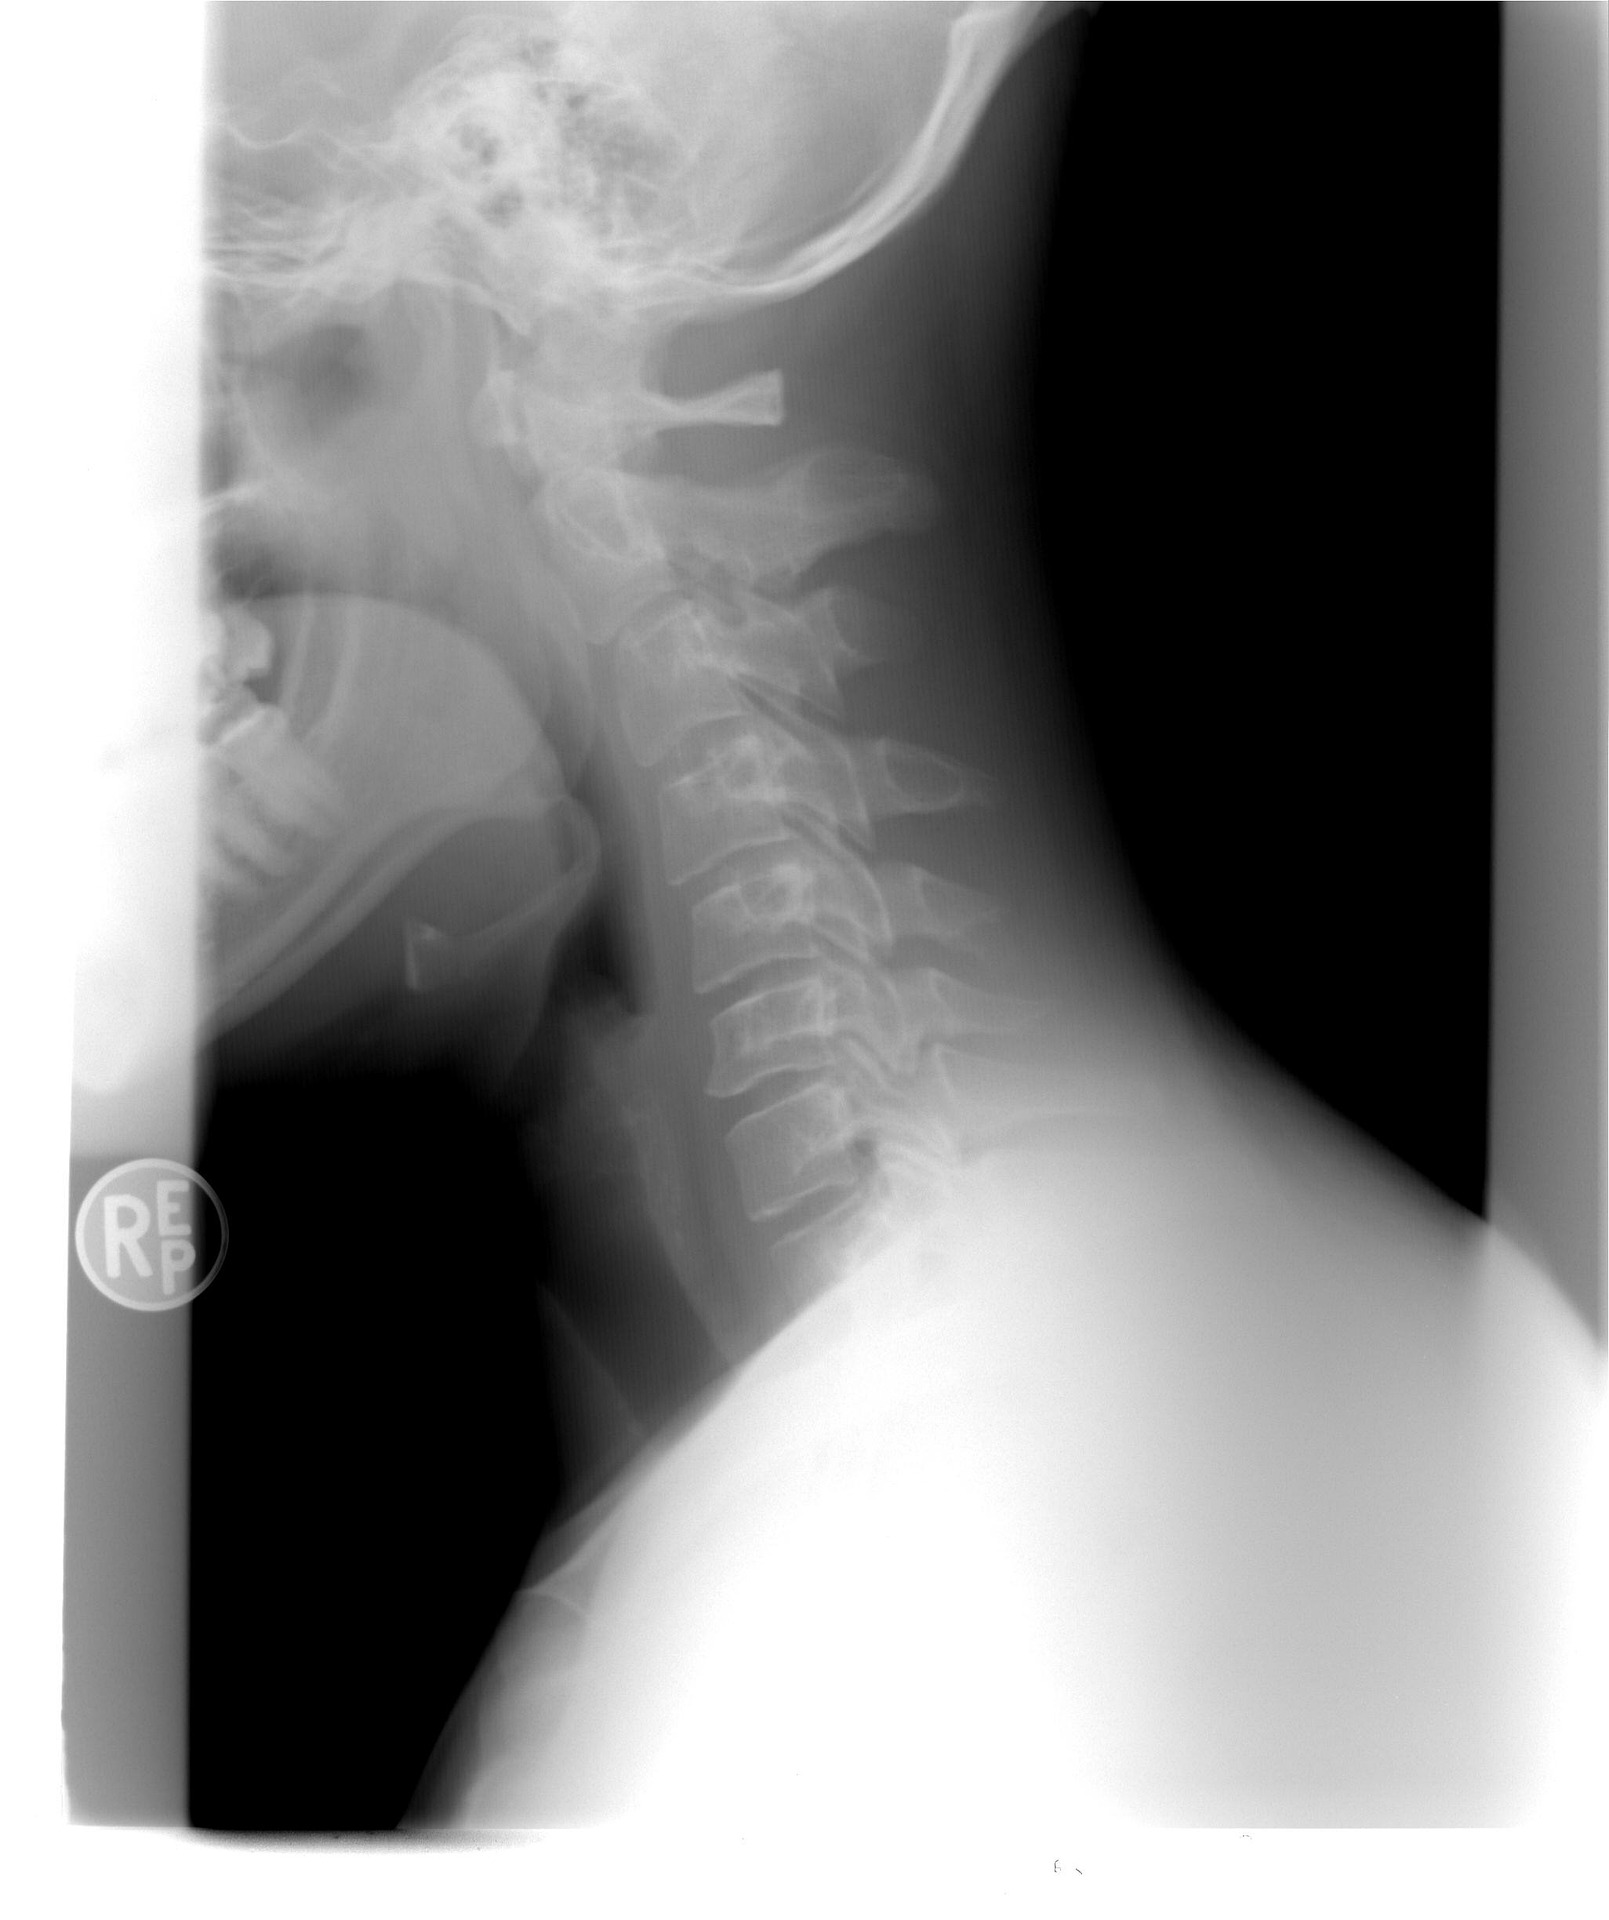

목은 머리를 지탱하고 움직임을 허용하는 신체의 복잡한 부분입니다. 목의 가장 중요한 구성 요소 중 하나는 7개의 척추와 추간판으로 구성된 경추입니다. 목디스크 문제는 통증, 뻣뻣함, 따끔 거림, 무감각, 목과 팔의 약화 등 다양한 증상을 유발할 수 있습니다.

경추는 7개의 경추와 추간판으로 구성되어 있습니다. 목디스크는 각 척추 사이에 위치하여 쿠션 역할을 하고 목을 움직일 수 있게 합니다. 목디스크는 섬유륜이라고 하는 거친 섬유질 조직의 외부 고리와 수핵이라고 하는 젤 같은 중심으로 구성됩니다.